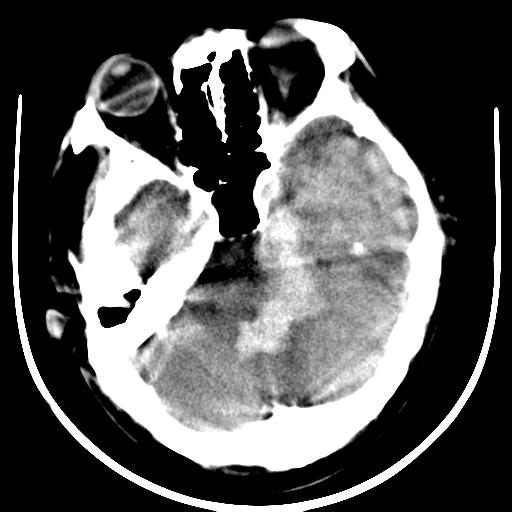

标题: CT16838:男58岁,意识不清2小时,请会诊出血部位该如何写。 [打印本页]

标题: CT16838:男58岁,意识不清2小时,请会诊出血部位该如何写。

1)脑干、左侧桥小脑臂及小脑蚓部出血破入蛛网膜下腔。2)左侧基底节区灶性出血,不排除钙化灶。3)脑室系统少量积血。4)脑积水。

(患者病情危重,出现不自主运动——是引起图像质量不佳的主要原因)

脑干左侧原发性脑出血破入脑室系统及蛛网膜下腔出血伴梗阻性脑积水。左侧基底节区原发性脑出血。脑萎缩。